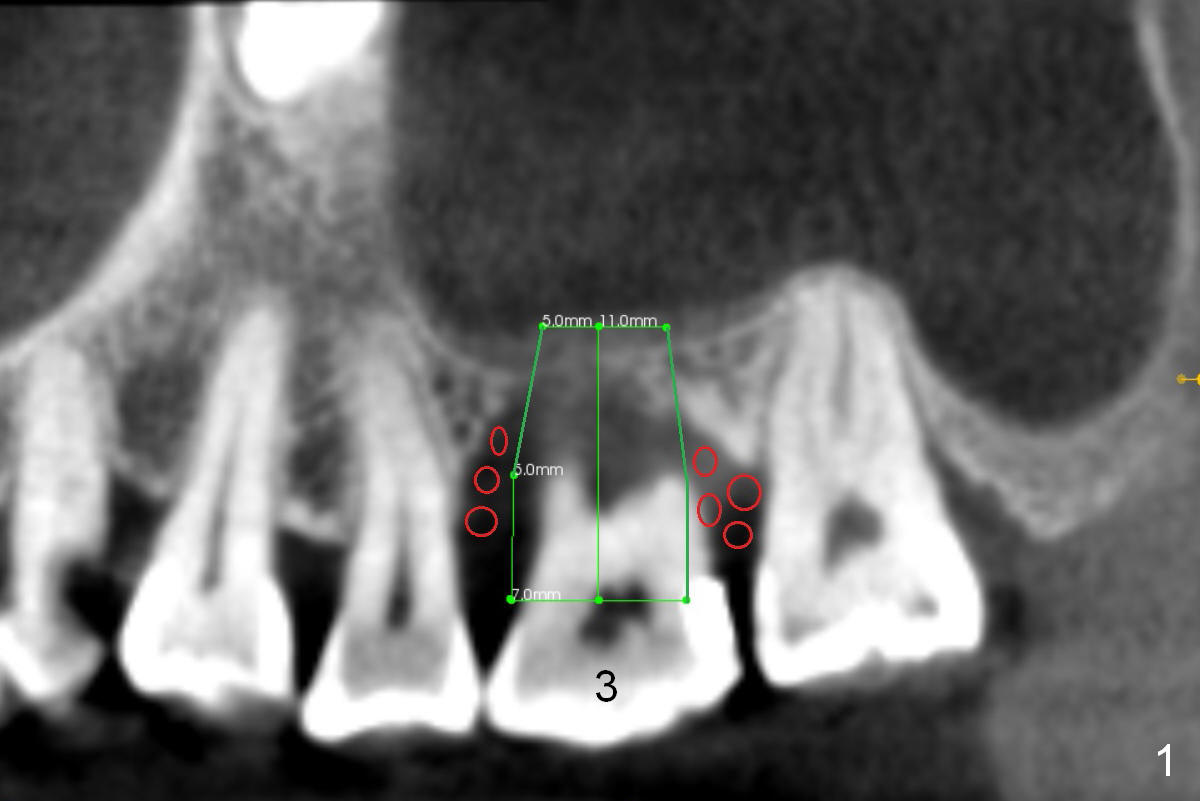

Immediate Implant for Periodontitis

A 52-year-old lady (ZJ) has severe bone loss at #3 (Fig.1 (CT sagittal section)). After extraction, the socket will be treated with Metronidazole. A small amount of apical bone is available for primary stability; the bone density is also low (300-500 Hounsfield Units, Fig.3 (axial section)). Use RT2,3 for creating osteotomy and bone condensation, followed by 4.5-7x14 mm taps (11 mm deep; gingival margin). Prior to bone grafting (Fig.1,2 (coronal section) red circles), apply Endogain against the root surface of the neighboring teeth.